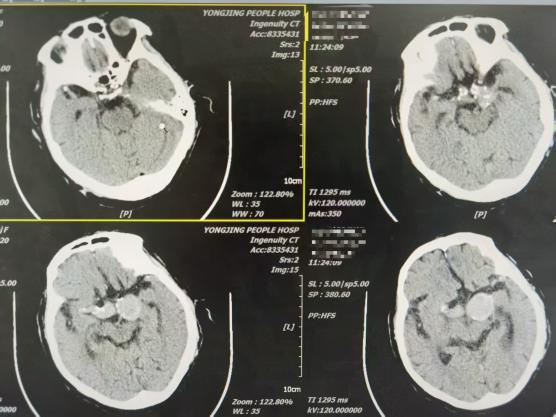

一位因反复头痛就诊的患者,经CT血管成像检查,确诊为颅内巨大动脉瘤,形态不规则,破裂风险极高。面对这一急危重症,孔令超与当地医生共同分析病情,制定诊疗方案。

通过对该病例影像特征的细致观察与风险分层评估,孔令超对巨大动脉瘤的形态学特点、破裂风险因素及介入治疗适应证有了更系统的认识。结合自身技术优势,完成全脑血管造影术,拓展了他在脑血管疾病领域的临床视野,也为科室今后开展动脉瘤介入治疗积累了宝贵经验。